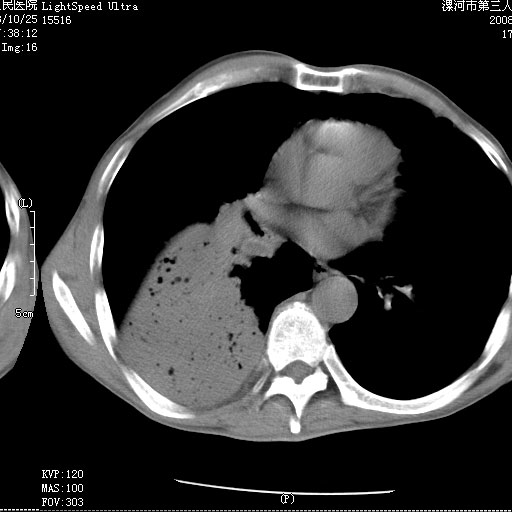

m 老年 发烧、呼吸困难,慢支、肺气肿多年;记的那次是下午大概17:38做的,晚上窒息死亡。

病灶边缘清---多个含气小腔---近端未见通畅气管影-----支持-----慢性肺脓肿继发阻塞性肺不张

阻塞性肺不张原因-----脓液未排出

3、细支气管肺泡癌可以排除,病变以斜裂为界,呈大片状高密度影,内可见多发小气泡,表明有产气杆菌感染所致,内无明显的支气管“枯树枝征”表现,再结合其临床改变(细支气管肺泡癌临表表现重、影像表现轻)所以不符合细支气管肺泡癌(炎症型)的改变。

右下肺实变,内有弥漫分面小气泡而无支气管征,叶间裂前移,呈臌大之形,而无收缩之状,兼纵隔稍左行移,故。不支持不张,倒支持大叶肺叶,如楼上所说,小气泡不象残留之肺,不可以考虑产气菌感染吗。

阻塞性肺炎,肺脓肿形成。依据,右下支气管不通,大片实变形内可见小气泡。不支持肺不张。

右下肺阻塞性炎症,内见多发气体影,以肺叶分布.不支持不张.

右肺下叶肺脓肿,右肺下叶支气管痰栓形成。